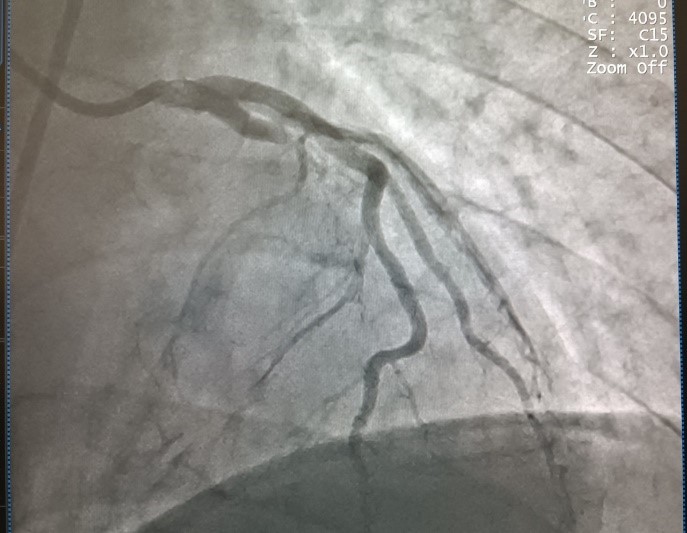

Sau đó, bệnh nhân được đưa vào phòng Can thiệp để tiến hành chụp động mạch vành và phát hiện có huyết khối gây tắc động mạch mũ, có chỉ định đặt stent. Tuy nhiên, trong quá trình can thiệp, bệnh nhân liên tiếp ngưng tim, ngưng thở thêm 4 lần nữa và rơi vào trạng thái hôn mê sâu. Để cứu sống bệnh nhân, Ê kíp bác sĩ vừa ép tim ngoài lồng ngực vừa sốc điện, vừa tiến hành can thiệp động mạch vành khẩn cấp cho bệnh nhân. Sau 10 phút nghẹt thở và căng thẳng, ê kíp các bác sĩ đã hồi sức cấp cứu và can thiệp thành công, lấy huyết khối, đặt stent tái thông động mạch vành cứu sống bệnh nhân.

Hình ảnh động mạch vành của bệnh nhân trước can thiệp